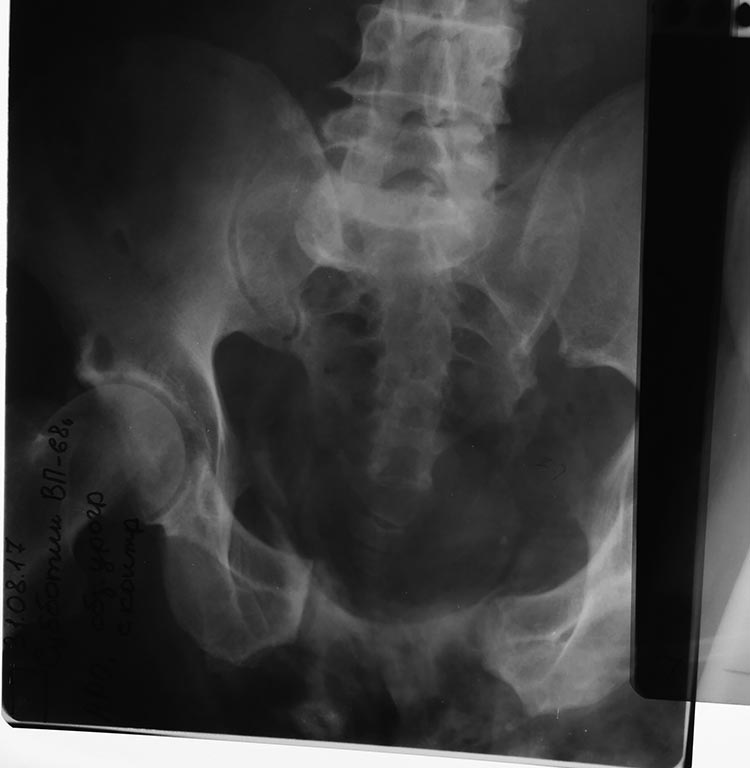

КТ

На КТ видно перелом верхней и нижней ветви лонной кости

В данной ситуации повреждение тазового кольца типа С.